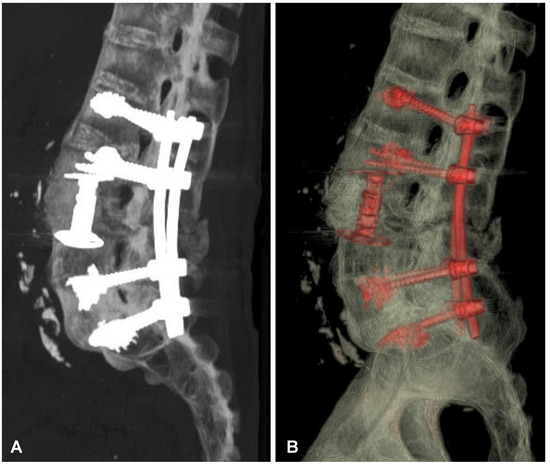

Figure 5. Postoperative sagittal CT scans (non-contrast enhanced) after the two-stage surgery of the lumbar spine demonstrating placement of the distractible vertebral body replacement implant between L3 and L4 (A) and posterior percutaneous transpedicular stabilization at the L2-L3-L5-S1 levels (B).

Figure 6. Postoperative CT-based reconstruction of the lumbar spine demonstrating correct positioning of the anterior and posterior spinal implants at the L2-L3-L5-S1 levels (A,B).

After initial diagnostics and preparations, the patient was transferred to the operating room. The posterior percutaneous transpedicular stabilization at the L2-L3-L5-S1 levels (Mantis; Stryker, Kalamazoo, MI, USA) with cement augmentation (VertaPlex HV; Stryker, Kalamazoo, MI, USA) for each inserted screw (4 mm × 6.5 mm/50 mm; 4 mm × 6.5 mm/45 mm) under intraoperative 2-dimensional (2-D) fluoroscopy control was performed in the first stage of surgery. In the second stage of surgery, from a lateral approach, the left side of the retroperitoneal cyst was emptied, and watery/light yellow fluid similar to urine was obtained. Therefore, a distractible vertebral body replacement implant (AsterX; Medtronic, Minneapolis, MN, USA) was placed between the L3 and L4 bodies with the placement of a retroperitoneal precutaneus Redon drainage system. A control CT scan performed one day after the operation revealed the correct placement of all the implants (Figure 5 and Figure 6). The second CE-CT scan performed two days after surgery consecutively showed evidence of post-traumatic right ureteral injury, urine leakage, and hydronephroureter (Figure 7). The general examination of intraoperatively obtained fluid revealed the following results: pH: 9.0; protein: 600 mg/dL; transparency and color before centrifugation: sanguine and cloudy; transparency and color before centrifugation: transparent and dark yellow; absolute leukocytes (LEU): 1197 cells/μL; and sediment: single round epithelium in the sample with erythrocytes loosely cover the field of vision (15–20 in the counterfield). The microbial culture of the intraoperative obtained fluid after 7 days was negative. After 4 days, the patient was transferred to another local hospital specializing in urological care. Due to the overall late presentation covering advanced hydronephrosis, ureteric stricture formation, and non-functional kidney, the nephrectomy and ureter ligation were performed. After urological treatment, the patient has been on follow-up for 2 years with no evidence of neurological or urological problems.